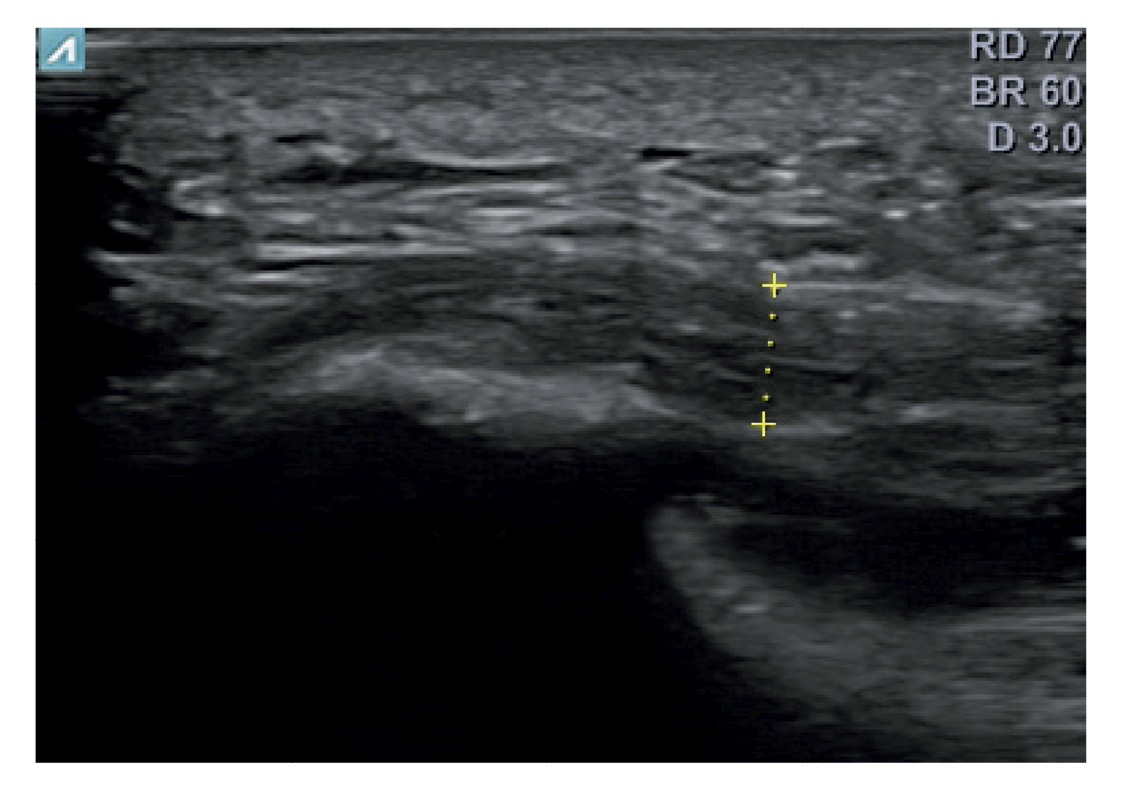

A todos los pacientes se les realizó una evaluación clínica y una evaluación ecográfica. La evaluación clínica se basó en una escala analógica visual (EVA) (13) (0-10) y el índice de función del pie (FFI) (14,15), que evalúa la función en una escala de 0 a 100. También se clasificó a los sujetos como sedentarios, activos o deportistas en función a su actividad física diaria, así como si era la primera vez que aparecía la enfermedad, era una recidiva o era crónica(16). También se evaluó el sexo, el peso y la talla, la presencia de vascularización en la fascia plantar visualizada con ecografía en el momento de la evaluación inicial y la forma biconvexa(17) o aplanada de la fascia plantar (Figura 1).

Figura 1. Fascia plantar con morfología normal a la izquierda y fascia plantar con morfología biconvexa a la derecha.